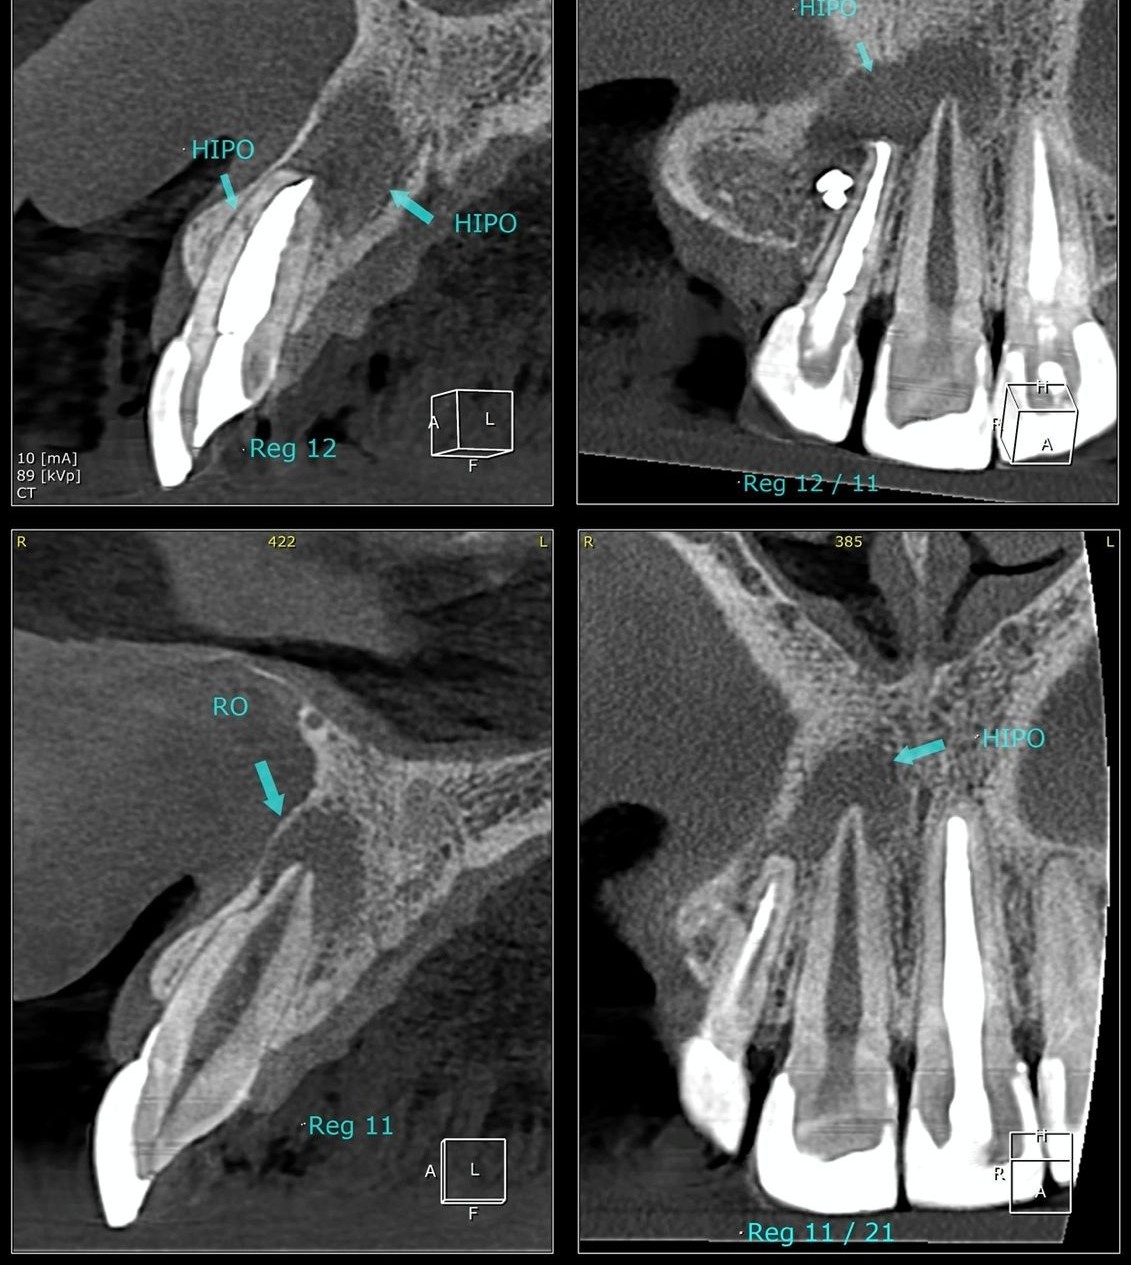

O diagnóstico da necessidade de uma apicectomia se baseia na avaliação clínica e nos exames de imagem. A radiografia e a tomografia computadorizada visualizam com precisão a extensão da lesão.

No caso citado, os exames mostraram claramente a presença de uma lesão no ápice do dente, tanto na região lateral quanto central da raiz, confirmando a necessidade de intervenção cirúrgica.